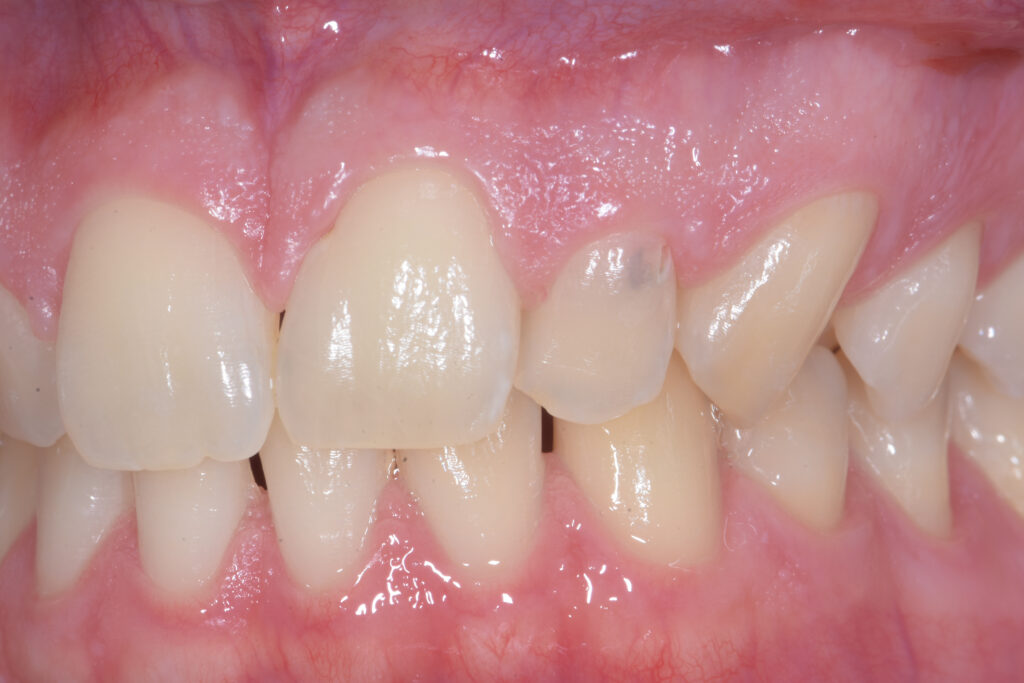

Il paziente si rivolge alla nostra attenzione lamentando un lieve inestetismo a carico dell’elemento 22 (Figura 1). Dopo la diagnosi, in questo caso prettamente clinica essendo la lesione vestibolare, viene proposto il trattamento congiunto chirurgico-conservativo come primo approccio, con l’obiettivo di mantenere per quanto possibile la vitalità dell’elemento dentale.